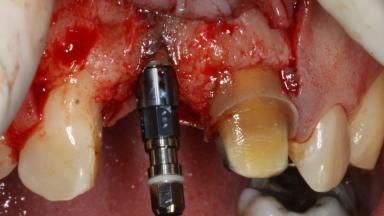

The patient presented with a failing tooth-supported fixed dental prosthesis with cantilever extension replacing the right maxillary central incisor. His chief presenting complaint was poor esthetics, in particular the dark discolored margin around the abutment tooth, the maxillary left central incisor. He reported a history of trauma at a young age, which necessitated the replacement of his maxillary right central incisor as well as root canal therapy of the adjacent left central incisor. The existing prosthesis had been in situ for over 20 years. The initial periapical radiograph displayed good proximal bone levels at the adjacent teeth and a wide incisive canal, which was a concern. The left central incisor presented a very wide root canal treatment with compromised radicular dentin thickness, which was a consideration in the decision between a new tooth-supported fixed dental prosthesis vs. an implant-supported prosthesis. After a lengthy discussion on the risks and benefits of both treatment options, the patient decided on a single-tooth implant replacement.

Bone Volume Deficient horizontally, allowing simultaneous augumentation